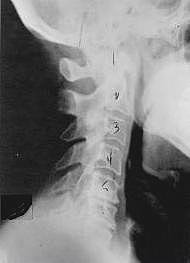

Near Normal

Subluxation Degeneration - Normal This is a side x-ray view of the neck. As with all the pictures you will see on this page, the patient is looking to the right of the screen, so you are viewing the right side of their neck. We will call this picture a "near normal" spine. Compare this spine with the ones you will see below on this page. Notice the normal forward curve of the neck. This curve helps absorb shock. Notice how each of the disc spaces between C2 (second bone in neck) and C7 are thick and even, this again is normal. Also notice how the front portions (right on the x-ray) of each of the vertebrae (called the 'body' of the vertebrae) are fairly square with clear and well defined borders. This type of arrangement is normal in the neck. Normal vertebrae in other parts of the spine also have similar characteristics to what we see here. When subluxations occur and are left uncorrected, ongoing relentless changes occur that result in damage to the structure and function of the spine along with nerve damage and the resulting problems caused from improper nerve supply.